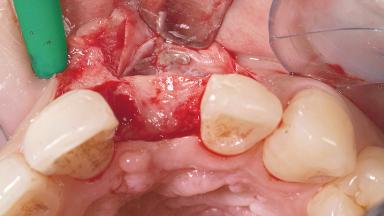

Late Placement of an Implant in a Maxillary Left Central Incisor Site

A 30-year-old female patient had lost tooth 21 and was referred to our clinic for consultation and treatment. Due to advanced apical infection, tooth 21 had been extracted two months earlier at another clinic and an acrylic-resin tooth had been bonded to the adjacent teeth. The patient desired implant treatment to avoid any damage to the adjacent natural teeth. While the patient had no history of any systemic disorder, she was a heavy smoker and exhibited medium to advanced periodontitis in the entire jaw. After the initial treatment to achieve a pocket probing depth of less than 4 mm and no bleeding on probing, a decrease in the height of the papillae mesial and distal to the extraction site and overall gingival recession were observed.

Bone Volume Deficient horizontally, requiring prior grafting